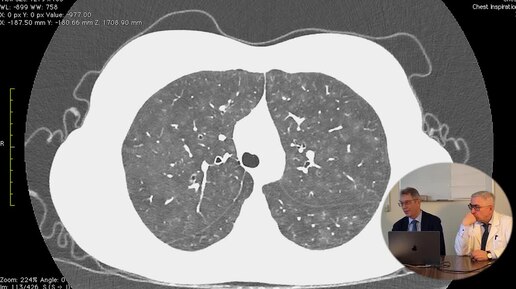

Попытка двух профессоров найти признаки пневмонии на низкокачественном КТ в негативе.